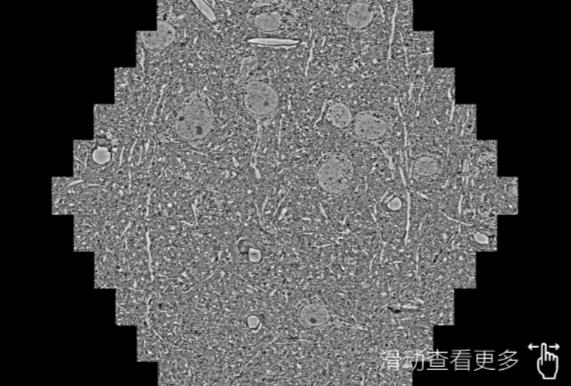

鼠脑切片。左图使用吉林蔡司吉林扫描电镜MultiSEM706对165μmx143pm面积区域成像,耗时仅需1.5秒。右图为鼠脑切片中30μm区域放大效果。样品由芝加哥大学B.Kasthuri提供。